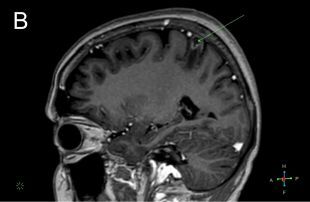

In recent years, there has been a steady increase in the number of people receiving immunosuppressive treatment. The ongoing development of these therapies, although effective in controlling autoimmune disease, brings with it new diagnostic and therapeutic challenges due to complex modulation of cellular and humoral responses. Despite significant therapeutic benefits, their use is associated with the risk of developing opportunistic infections, which are almost unrecognised in immunocompetent persons. We present a case of neuroinfection caused by Listeria monocytogenes complicated by brain abscess in an autoimmune hepatitis female patient treated with prednisone and mercaptopurine. Importantly, the disease initially presented with non-specific neurological symptoms, which might have delayed diagnosis. Nevertheless, an early lumbar puncture, cerebrospinal fluid testing with identification of the most common pathogens, and imaging tests allowed for diagnosis and implementation of appropriate antibiotic therapy, which resulted in the expected clinical improvement. This case highlights that patients receiving immunosuppressive therapy may develop serious opportunistic infections, and early diagnosis and implementation of right treatment are crucial for improving prognosis and minimising complications.